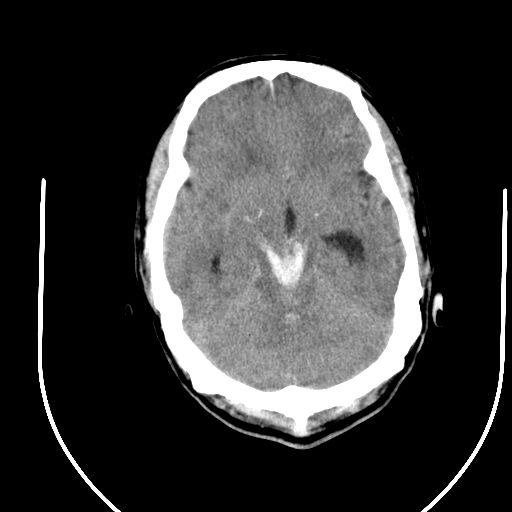

标题: CT24997:M,60Y,突发昏迷30分钟,有高血压病史。 [打印本页]

标题: CT24997:M,60Y,突发昏迷30分钟,有高血压病史。

1右侧基底节脑出血伴脑干出血并破入脑室系统脑疝形成2梗阻性脑积水

1)右侧基底节脑出血伴脑干出血并破入脑室系统。2)大脑镰下疝。3)梗阻性脑积水。

1、右侧基底节脑出血伴脑干出血并破入脑室系统。

2、大脑镰下疝。

3、梗阻性脑积水。